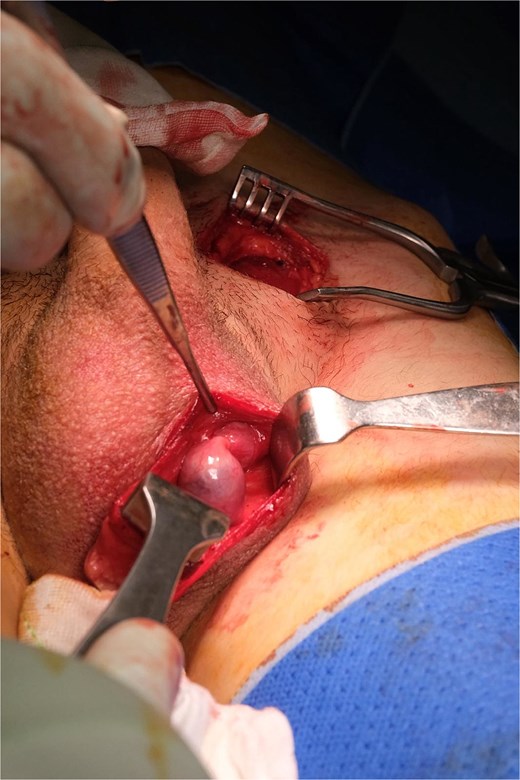

An elongated gubernaculum tethered high in the scrotum was also noted (Fig. 4). Following careful dissection, the testis was freed, revealing a viable appearance and adequate cord length for scrotal mobilization (Fig. 5). A subdartos pouch was created via a left paramedian scrotal incision, and the testis was delivered into the scrotum via a tunnel created by gentle blunt dissection (Fig. 6). The testis was fixated in three-points with a 4-0 polydioxanone suture. The contralateral hemiscrotum was also explored utilizing the same incision, where the right testis was found to have a normal lie and attachments. It was likewise fixated.

Left testis following adhesiolysis, demonstrating an elongated gubernaculum tethered high in the scrotum.

Completely mobilized left testis, showing viable appearance and adequate cord length for tension-free mobilization.